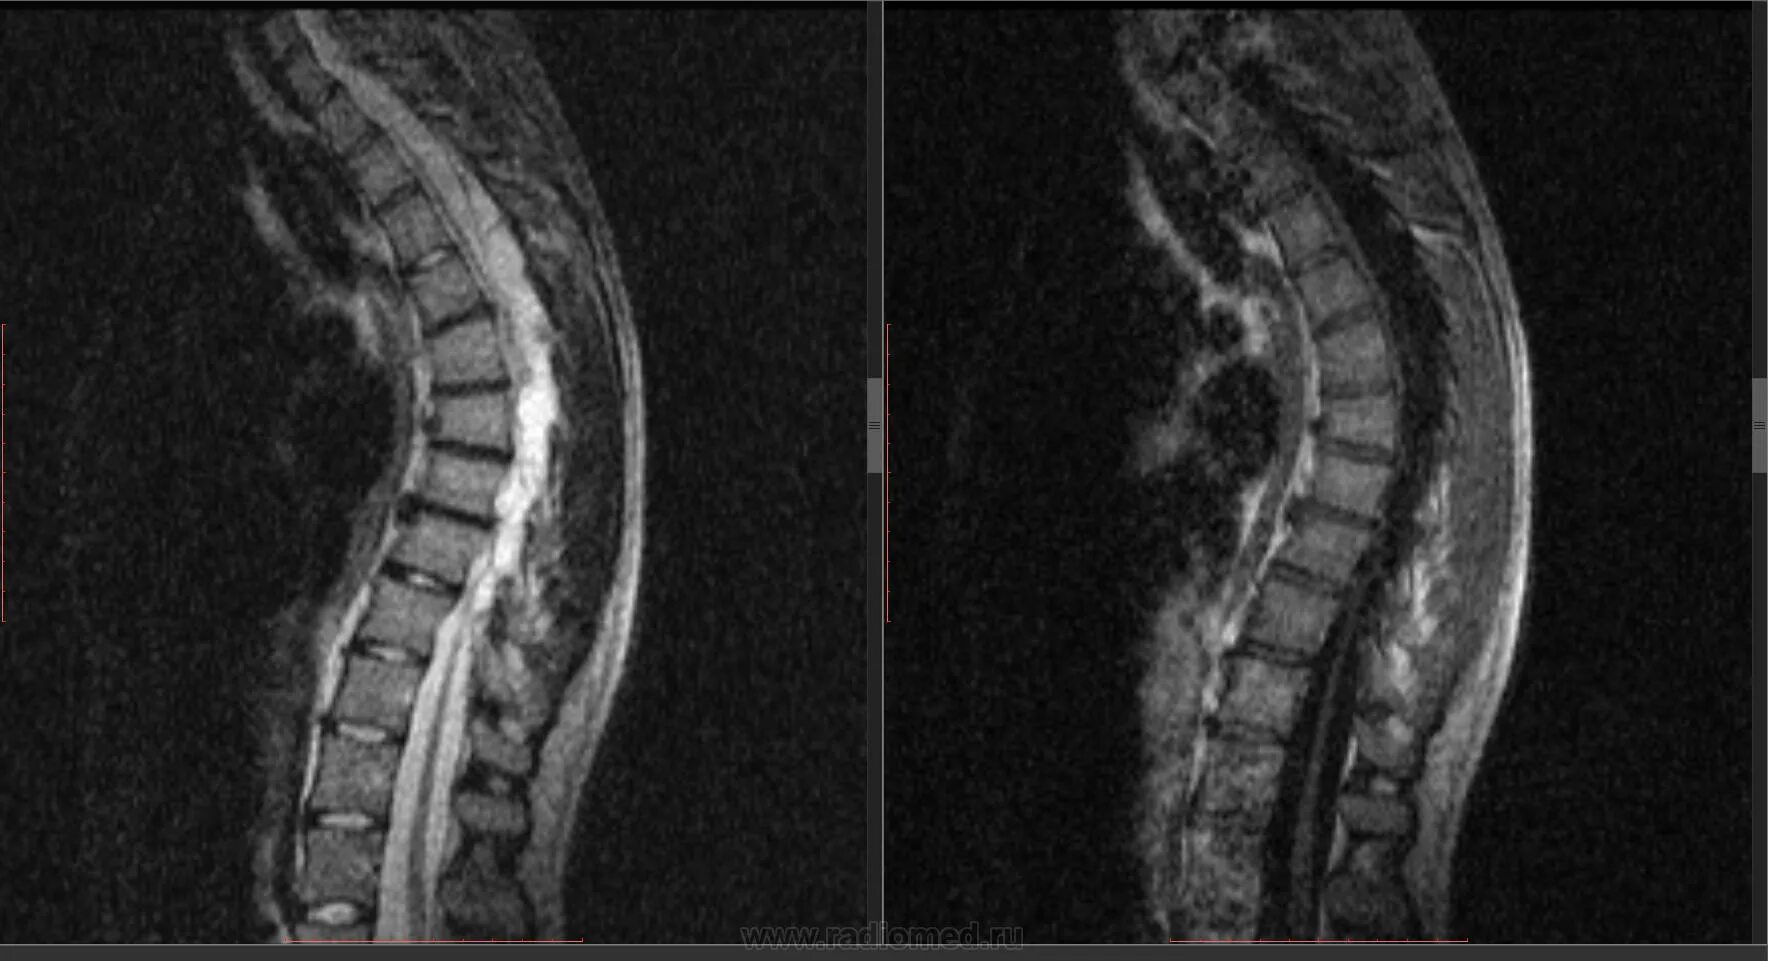

Киста в грудном отделе позвоночника